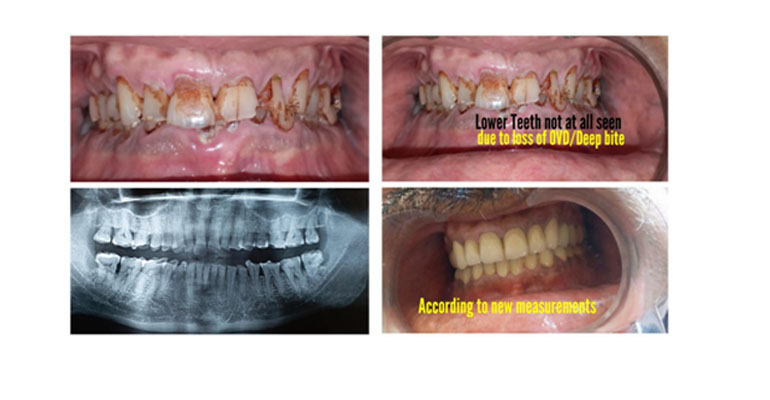

Here as you see the double chin appearance is corrected, patient looks younger and vertical of the height is raised and muscles look toned up too. All the above images are of one case presentation.